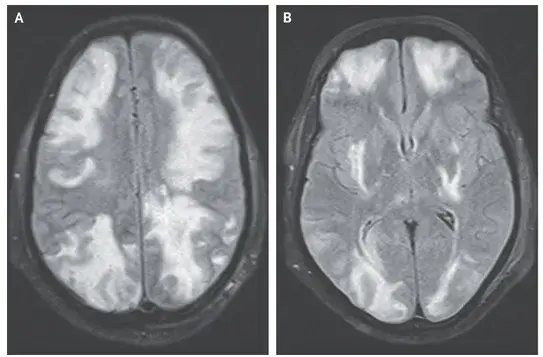

Caso clínico publicado no NEJM: Um homem de 35 anos com nefropatia por IgA procurou pronto-socorro com quadro de confusão mental, visão embaçada e convulsão há 01 dia. Duas semanas antes da apresentação ele começou a tomar ciclosporina para tratamento de nefropatia por IgA. Sua PA era de 160/80 mm Hg. Ao exame físico paciente